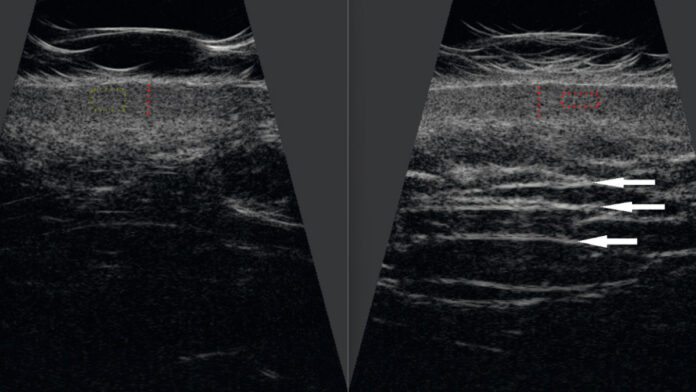

Celem badania była ocena skuteczności terapii z wykorzystaniem iniekcji dwóch preparatów kwasu hialuronowego o wysokiej masie cząsteczkowej oraz analiza ich wpływu na grubość i właściwości skóry z oznakami starzenia u czterech kobiet w wieku 35-46 lat.

Terapia przyniosła poprawę nawilżenia, elastyczności i jędrności skóry, wspierając jednocześnie jej naturalne procesy regeneracyjne. Potwierdzono to utrzymującym się wzrostem grubości i gęstości skóry właściwej. Uzyskane efekty były trwałe i widoczne jeszcze co najmniej miesiąc po zakończeniu serii zabiegów.

The study aimed to evaluate the effectiveness of a therapy using injections of two high molecular weight hyaluronic acid preparations and to analyze their influence on the thickness and properties of skin with signs of aging in four women aged 35-46.

The therapy improved skin hydration, elasticity, and firmness, while supporting its natural regenerative processes. This was confirmed by a sustained increase in the thickness and density of the dermis. The effects obtained were longlasting and visible for at least one month after the end of the treatment series.